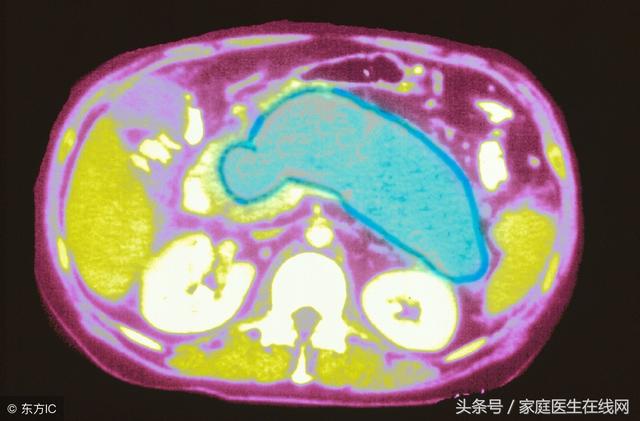

首先,胰腺炎是胰腺因胰蛋白酶的自身消化作用而引起的疾病。

其次,胰腺有水肿、充血,或出血、坏死。临床上出现腹痛、腹胀、恶心、呕吐、发热等症状。化验血和尿中淀粉酶含量升高等。可分为急性及慢性二种。

胰腺在大家的体内是非常重要的器官之一,胰腺的主要功能就是分泌胰液,就可以帮助大家去消化吃进去的食物,要是体内的胰液被错误激活之后,消化的对象就不在是吃进去的食物了,而是效果胰腺自身或者是消化旁边的器官,这就是胰腺炎发生的原因了。